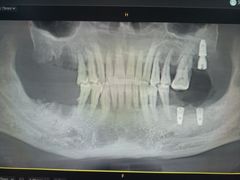

• 牙博士口腔品牌连锁(杨浦店)

• -牙博士口腔品牌连锁(杨浦店)